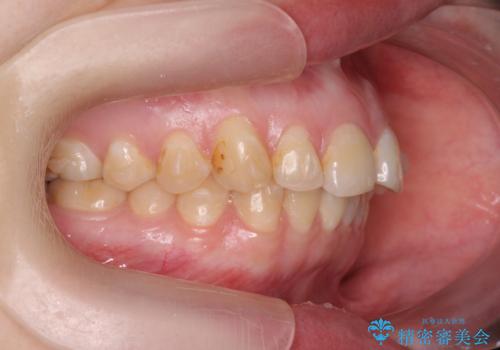

マウスピース矯正で行う出っ歯の治療

- 飛び出したように見える前歯の改善を求めて来院されました。

元々、セラミッククラウンですぐに歯並びを改善したいと希望されていましたが、目立たないマウスピース矯正治療のご提案を行なったところ矯正治療による歯並びの改善を選択されました。

矯正治療を行ったことで出っ歯の改善とともに安定した噛み合わせも手に入れることができました。